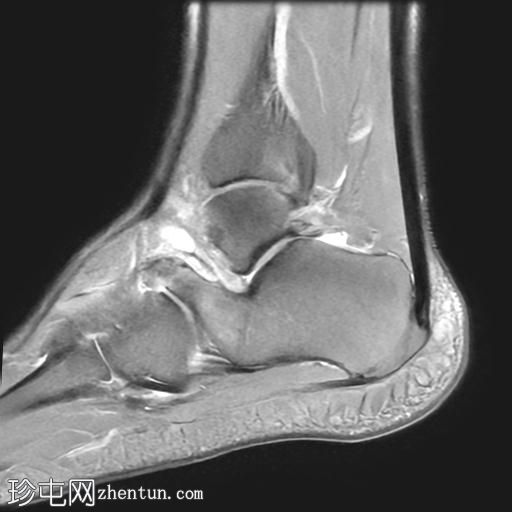

MRI

矢状位

PD脂肪抑制序列

冠状位

T1加权像

冠状位PD脂肪抑制序列

轴位

T2加权像

跟骨前突延长增宽,与舟骨形成不规则关节,形似“食蚁兽

鼻

”。

该异常跟舟关节处可见关节下骨髓水肿。此外,舟骨内外侧径增宽,向外侧逐渐变细,并与增大的跟骨前突形成关节。

距舟关节轻度积液,并可见边缘骨赘。